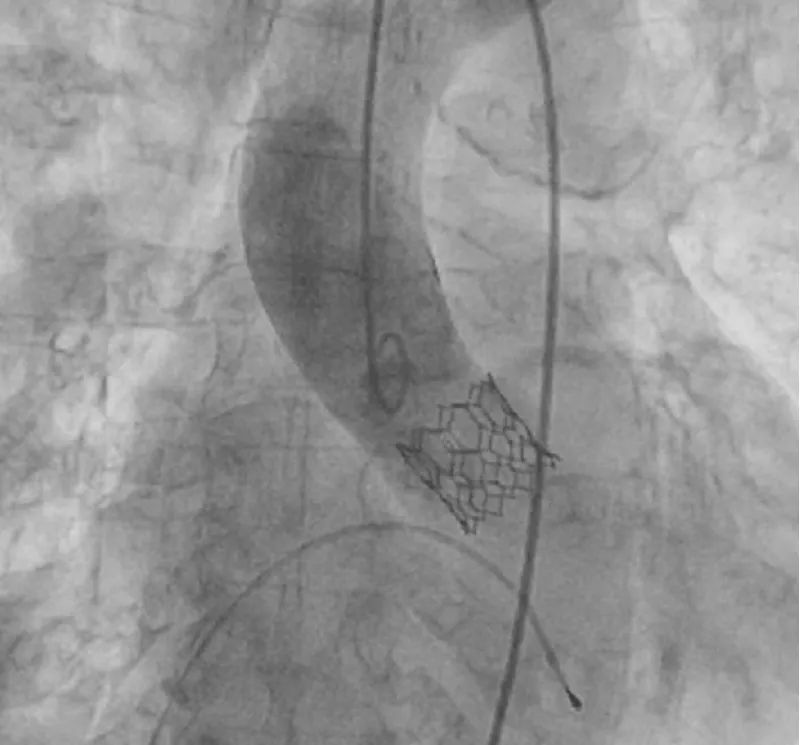

Procedural success was achieved in 100% of patients. The majority of procedures were performed under local anesthesia and/or conscious sedation, except when general anesthesia was required for a surgical cut to access the common femoral artery. The TF approach was achieved in 100% of cases and percutaneous in 92.3%. The valve was directly implanted in 10 patients, while the native aortic valve was predicated in three patients. Intermediate sizes of Myval THV were implanted in 46.16% of patients while extra-large Myval THV was implanted in 15.38% of patients. Post-TAVI, clinically significant PVL was not observed. Table 2 summarizes the procedural outcomes. Figure 2 depicts the typical image of the Myval THV system deployed orthotopically with no PVL.

Figure 2: A representative of an aortic CT angiogram of intermediate-size 21.5 mm Myval THV deployed orthotopically without paravalvular leakage.